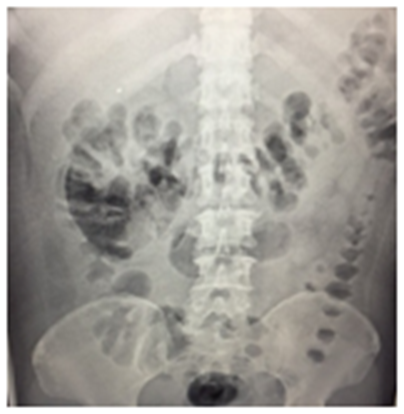

We present the case of a 47-year-old female admitted to emergency department for a 4day disease characterized by fever, chills, adynamia, asthenia and right flank pain of moderate intensity. Past day she refers hematemesis in an occasion. She denied pathologic background. At physical examination she presents with 39ºC, arterial tension 90/60mmHg, 95 hearths per minute, 23 breaths per minute, saturation 91%, right flank pain, positive Giordano sign and positive superior ureteral points, without signs of peritoneal irritation. Laboratories report withe blood cells 13000/mm3, neutrophils 92%, Hemoglobin 13.7g/dL, Platelets 82000, Glucose 595mg/dL, Cr 2mg/dL. Gas Analysis report pH 7.28 HCO3-7 mmol/L BEecf -19.7mmol/L, SO2 88%. Urinalysis report leucocytes >75μL, uncountable red blood cells, bacteries +++, nitrites+++ Glucose +++, proteins +, ketones ++. Pyelonephritis and Diabetes mellitus2 of recent diagnosis was established. After twodays of medical treatment she presented septic shock with acute renal failure AKIN II, hematological and hepatic disfunction. Mechanic ventilatory support and use of norepinephrine were adhere to therapy. Laboratories report with blood cells 8400/mm3, neutrophils 82%, Hemoglobin 9.5g/dL, Platelets 57000, Glucose 595mg/dL, Cr 2mg/dL, total bilirubin 6.3mg/dL, lactic dehydrogenase 572 U/l, alanine aminotransferase 352 U/l. This case was present in a rural hospital and the unique imaging auxiliary available was an abdomen X-ray that shows an air bubble in the right perirenal space (Figure 1). Emphysematous pyelonephritis was diagnosed and urgent right nephrectomy performed after platelet transfusion. The surgery was successful and without complications finding a right kidney of 9x6x4 centimeters with multiple parenchymal abscesses (Figure 2). After 6days extubation was achieved by internal medicine service and after 5days the patient was discharged uneventfully.

Figure 1 A) Abdomen X-ray showing a bubble in the perirenal right space.

Emphysematous pyelonephritis (EP) is more common among females than males (3:1) with left side involvement in 60% of cases.3 It is a rare life-threatening infection producing abscess with intrarenal gas, vasculitis, intravascular hemolysis, thrombosis with infarction, papillary necrosis and glomerular sclerosis. It will presents with symptoms like fever, pain and pyuria in about 70% of cases. When septic shock was present it was associated with a mortality of 54.4% in some studies and it should be managed promptly with a multidisciplinary approach.3 Mortality rate is about 18% and must be suspected in Diabetic patients with acute pyelonephritis poor response to medical treatment, otherwise the clinical course may be life-threatening if not recognized.2 The presentation of this entity in Diabetic patients is secondary to the hydrogen and carbon dioxide release through sugar fermentation by the higher glucose concentrations in tissues, which favors the growth of microorganisms4 including E. coli in 51%, followed by Klebsiella 18% and Pseudomonas 13%5. Thrombocytopenia, acute renal failure, shock and conservative treatment have been identified as significant risk factors for mortality.5,6 Diabetic ketoacidosis (DKA) is an uncommon presentation; only few cases of DKA and EP have been reported in the literature. The finding of gas within renal structures is pathognomonic of EP.7 The clinical presentation and laboratory findings must represent an acute pyelonephritis and for this reason the diagnosis requires imaging studies. In X-ray images gas bubbles are observed on renal parenchyma or perirenal tissues, psoas muscle is effaced. Ultrasound must be inadequate in settle down EP diagnosis.4 Computed Tomography (CT) scanning is the gold standard to diagnosis and classification, this last based on the extension of gas and location around the kidney7 (Table 1).